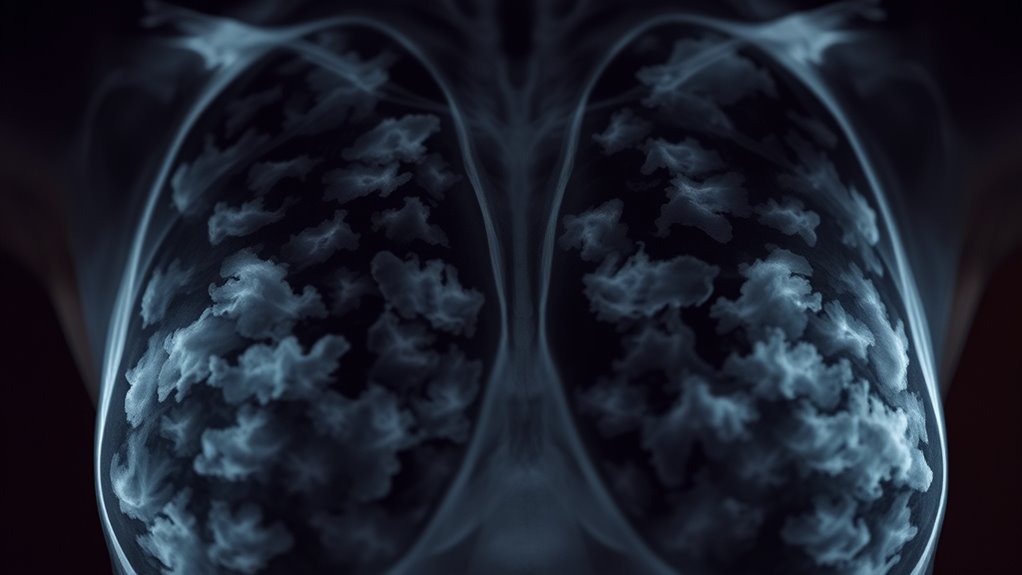

Die Wirksamkeit der Mammographie nimmt bei dichtem Brustgewebe ab, was häufig dazu führt, dass Tumoren übersehen werden und falsche Negative auftreten, wodurch die Ergebnisse irreführend sein können. Sonographie hilft, indem sie Krebsarten erkennt, die Mammographien möglicherweise übersehen, insbesondere bei dichtem Brustgewebe, hat aber ebenfalls ihre Grenzen. Beide Bildgebungsverfahren können manchmal irreführende Ergebnisse liefern, wenn sie allein verwendet werden. Das Verständnis dafür, wann diese Methoden irreführen können, hilft Ihnen bei der Entscheidung für zusätzliche Screening-Optionen – erfahren Sie mehr darüber, wie Sie diese Herausforderungen effektiv bewältigen können.

Das Verständnis der Empfindlichkeit der Mammographie ist entscheidend, da sie bestimmt, wie effektiv dieses bildgebende Verfahren Brustkrebs erkennen kann. Es ist wichtig zu wissen, dass die Gesamtempfindlichkeit der Mammographie bei etwa 85 % liegt, aber bei dichtem Brustgewebe deutlich sinkt, manchmal unter 65 %. Dichtes Gewebe erschwert es den Röntgenstrahlen, Tumore zu unterscheiden, was zu übersehenen Diagnosen führen kann. Außerdem ist die Mammographie bei älteren Frauen wirksamer, da deren Brüste tendenziell weniger dicht sind. Während Mammografien etwa 75 % der häufig vorkommenden Krebserkrankungen erkennen, werden dennoch einige übersehen, insbesondere bei jüngeren Frauen oder solchen mit dichtem Brustgewebe. Es ist wichtig zu beachten, dass diese Einschränkungen bedeuten, dass ein negatives Mammogramm nicht immer Krebs ausschließt, was die Bedeutung zusätzlicher Untersuchungsmethoden für Hochrisikogruppen unterstreicht. Dichte des Brustgewebes kann die diagnostische Genauigkeit erheblich beeinflussen und die Notwendigkeit personalisierter Screening-Strategien betonen.

Brustdichte spielt eine bedeutende Rolle bei der Wirksamkeit von Bildgebungsverfahren zur Krebsfrüherkennung. Dichtes Gewebe kann Tumoren auf Mammographien verdecken und somit deren Genauigkeit verringern, insbesondere bei jüngeren Frauen. Das Verständnis darüber, wie die Gewebezusammensetzung die Bildgebung beeinflusst, hilft Ihnen dabei, die beste Vorsorgemethode auszuwählen.

Dichtes Brustgewebe stellt eine bedeutende Herausforderung für die Bildgebung dar, da es Tumore auf Mammographien verdecken kann, was zu verpassten oder verzögerten Diagnosen führt. Je höher die Dichte, desto schwieriger ist es, krebsartige Veränderungen vom umliegenden Gewebe zu unterscheiden. Die Empfindlichkeit der Mammographie sinkt bei dichten Brüsten deutlich, oft werden fast die Hälfte der Krebserkrankungen in solchen Fällen übersehen. Dadurch können Sie ein falsches Sicherheitsgefühl haben, obwohl bereits ein Tumor vorhanden ist. Ultraschall wird hier wertvoll, da er Krebsarten erkennen kann, die in dichtem Gewebe von der Mammografie übersehen werden. Eine alleinige Mammografie kann Sie jedoch anfällig für Intervalleingriffe machen, die schlechtere Ergebnisse haben. Um die Erkennung zu verbessern, wird häufig eine zusätzliche Bildgebung mit Ultraschall für Frauen mit dichten Brüsten empfohlen. Außerdem kann das Verständnis der steuerlichen Besonderheiten in den Bundesländern die Gesamtkosten für Screening und Nachsorge beeinflussen, insbesondere wenn zusätzliche Bildgebungsverfahren in Betracht gezogen werden.